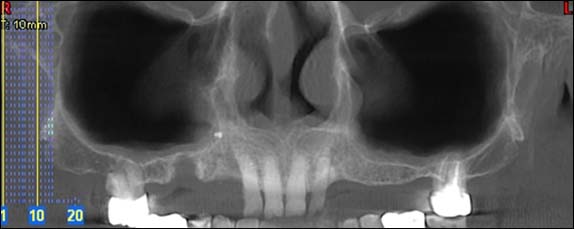

PANORAMIQUE :

TÉLÉRADIOGRAPHIE DE PROFIL ET DE FACE :